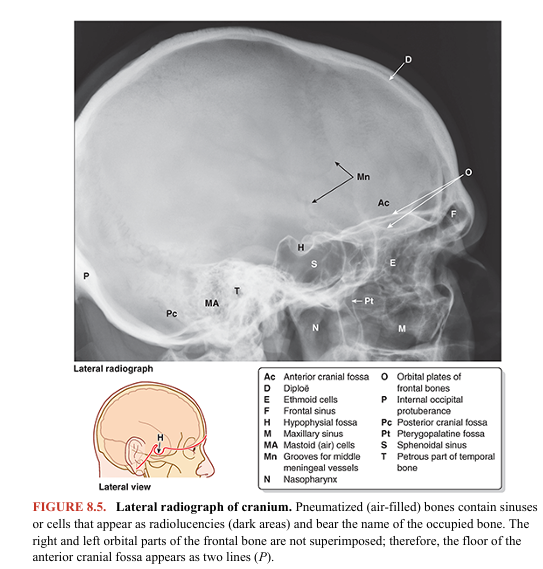

Several bones of the cranium (frontal, temporal, sphenoid, and ethmoid bones) are pneumatized bones, which contain air spaces (air cells or large sinuses), presumably to decrease their weight (Fig. 8.5). The total volume of the air spaces in these bones increases with age.

The walls of the cranial cavity vary in thickness in different regions. They are usually thinner in females than in males and are thinner in children and elderly people. The bones tend to be thinnest in areas that are well covered with muscles, such as the squamous part of the temporal bone (Fig. 8.11). Thin areas of bone can be seen radiographically (Fig. 8.5) or by holding a dried cranium up to a bright light. Most bones of the calvaria consist of internal and external tables of compact bone, separated by diploë (Figs. 8.5 and 8.11). The diploë is cancellous bone containing red bone marrow during life, through which run canals formed by diploic veins. The diploë in a dried calvaria is not red because the protein was removed during preparation of the cranium. The internal table of bone is thinner than the external table, and in some areas, there is only a thin plate of compact bone with no diploë. The bony substance of the cranium is unequally distributed. Relatively thin (but mostly curved) flat bones provide the necessary strength to maintain cavities and protect their contents. However, in addition to housing the brain, the bones of the neurocranium (and processes from them) provide proximal attachment for the strong muscles of mastication that attach distally to the mandible. Consequently, high compressive forces occur across the nasal cavity and orbits that are sandwiched between. Therefore, thickened portions of the cranial bones form stronger pillars or buttresses that transmit forces, bypassing the orbits and nasal cavity (Fig. 8.13). The main buttresses are the frontonasal buttress, extending from the region of the canine teeth between the nasal and the orbital cavities to the central frontal bone, and the zygomatic arch–lateral orbital margin buttress from the region of the molars to the lateral frontal and temporal bones. Similarly, occipital buttresses transmit forces received lateral to the foramen magnum from the vertebral column. Perhaps to compensate for the denser bone required for these buttresses, some areas of the cranium not as mechanically stressed become pneumatized (air filled).